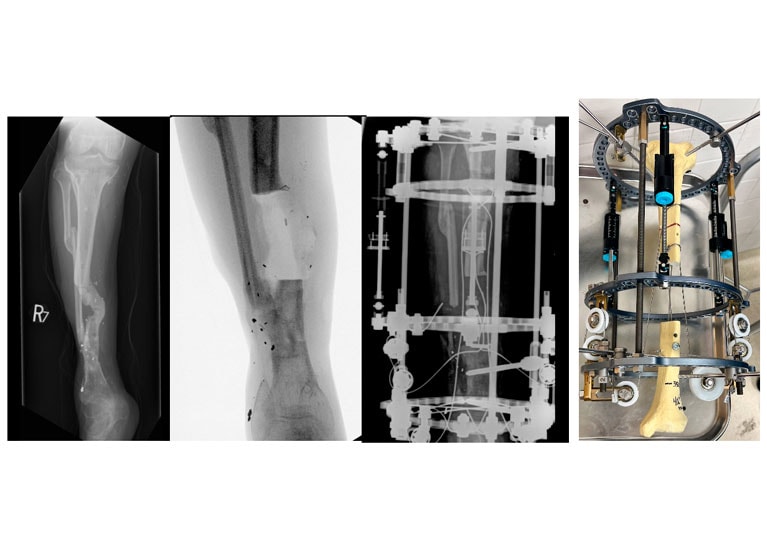

Automated external circular frame and intramedullary cables Automated external circular frame and intramedullary cables

Tibia with automated external circular frame and intramedullary cables: bone transport.